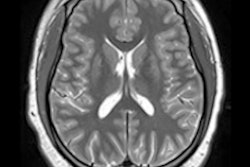

Examples of axial FLAIR sequences from studies within dataset A. From left to right: a patient with a "likely normal" brain, a patient presenting an intraparenchymal hemorrhage within the right temporal lobe, a patient presenting an acute infarct of the inferior division of the right middle cerebral artery, and a patient with known neurocysticercosis presenting a rounded cystic lesion in the left middle frontal gyrus. Image and caption courtesy of RSNA."[Our study shows] promising results ... when comparing model performance to annotations from the radiologic reports, indicating that such an approach could be used to build a triage system for MRI brain examinations," the group noted.